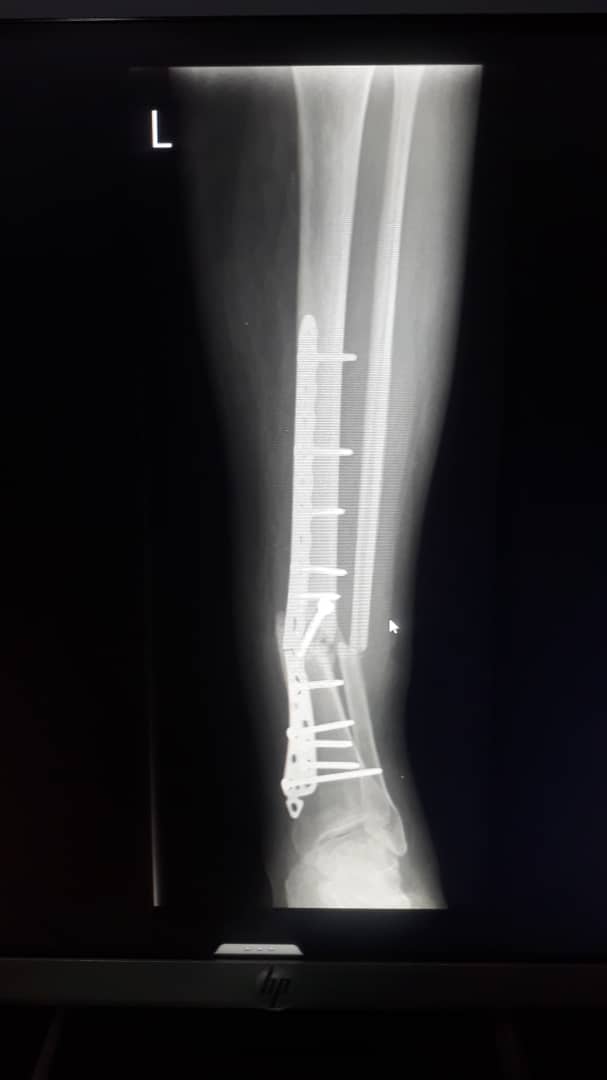

A broken screw implant attached to the Tibia fracture and a surgery is needed

A broken screw implant needs to be operated out of a broken Tibia/fibula fracture.